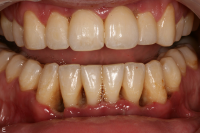

En bakteriellt orsakad inflammation som leder till en progressiv förlust av tändernas stödjevävnader.

Diagnostik

Det viktigaste måttet att påvisa sjukdom i parodontala vävnader är blödning.

- Gingivit blödning vid sondering, ingen benförlust, fickdjup 3 mm eller mindre. Parodontitis superficialis: fickdjup 5 mm eller mindre, horisontell och/eller angulär benförlust mer än 2 mm och blödning/pus vid sondering.

- Parodontitis profundus fickdjup 6 mm eller mer, horisontell och/eller angulär benförlust mer än 2 mm och blödning/pus vid sondering.